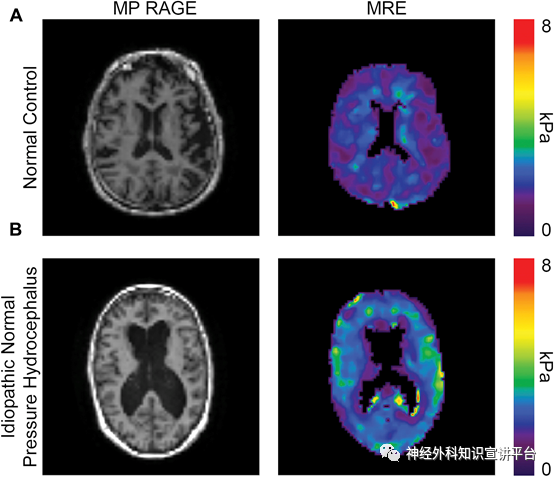

MRE(弹性磁共振)显示常压性脑积水病人局部脑组织弹性差,顺应性降低。